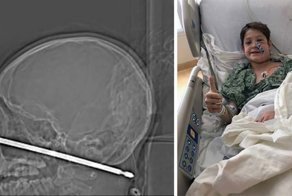

Эбби и Эрин Дилани из Северной Каролины, - сиамские близнецы. Они родились сросшимися головами в районе макушки, с объединенным мозгом. Операция по их разделению в филадельфийском госпитале длилась 11 часов и была, по признанию хирургов, одной из самых сложных операций по разделению сиамских близнецов. Ее результат никто не мог предсказать: врачи предупредили родителей, что операция рискованная, и что, скорее всего, одна из девочек умрет под ножом хирурга. Однако теперь, спустя полтора года после операции, обе девочки, ко всеобщему изумлению, развиваются точно так же, как их обычные сверстники.

Эрин и Эбби родились 24 июня 2016 года путем кесарева сечения. Подобные сиамские близнецы - краниопаги, сросшиеся черепами, - появляются на свет чрезвычайно редко. Они появились на свет на 10 недель раньше срока, при этом каждая весила около килограмма. Операция по их разделению была произведена в детском госпитале Филадельфии 7 июля 2017-го, когда девочкам было по 11 месяцев. Это была одна из самых ранних в истории операций такого рода.

После операции Эрин выздоравливала быстрее, поскольку большая часть ее черепа осталась неповрежденной. Эбби пришлось хуже: она боролась и с мозговым кровотечением, и с многочисленными инфекциями. Сейчас врачи утверждают, что спокойны за их будущее. Но перед операцией они предупреждали родителей девочек, Хизер и Райли Дилани, что одна или даже обе девочки, скорее всего, погибнут в результате операции. "Это страшно, и мы были напуганы, но мы не могли позволить страху помешать нам оперировать", - говорит нейрохирург Грегори Хейер.

Перед операцией врачи вживили под кожу голов девочек эластичные шары, чтобы растянуть кожу и впоследствии использовать излишек для закрытия головы. Хирурги выполнили операцию чрезвычайно рано, поскольку у маленьких детей больше шансов не только пережить подобное хирургическое вмешательство, но и полностью восстановиться после него.

В детском госпитале Филадельфии прежде были сделаны 24 операции по разделению сиамских близнецов. В команде, занимающейся такими операциями, здесь работает около 30 человек. В ходе операции Эбби чуть не умерла из-за массивного кровотечения после того, как была отделена от сестры. Из-за особенностей сращения сестер сагиттальный синус остался на голове Эрин, а именно эта структура мозговой оболочки отвечает за отвод крови от мозга и костей черепа. В дальнейшие месяцы это сильно осложнило выздоровление Эбби.